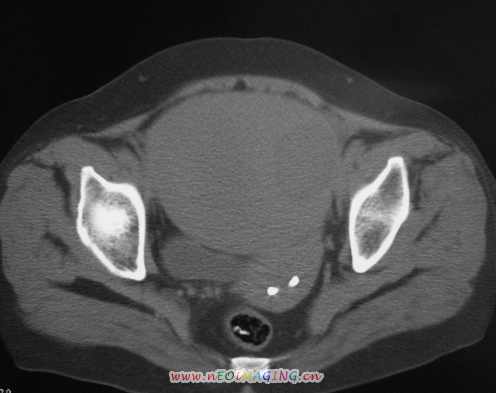

标题: CT11527:女56岁以右输尿管结石入院

女56岁以右输尿管结石入院

病灶位于下腹部盆腔,从子宫与膀胱明显受压后移看,应该来源于盆腹腔的占位,病灶实性部分密度均匀,左侧可见低密度灶,建议增强扫描,考虑:间叶性肿瘤,或硬纤维瘤,输尿管下段结石伴上段输尿管扩张

右侧盆腔占位,考虑来源于卵巢,囊腺瘤可能性大。

右侧输尿管结石。

1)盆腔占位性病变,考虑来源于卵巢,囊腺瘤可能性大。2)右侧输尿管第二狭窄处结石伴梗阻。

今天病人已经手术证实为右附件囊肿,右侧输尿管第二狭窄处结石伴梗阻!!!

[病理诊断] CT11527:右附件囊肿,右侧输尿管结石。